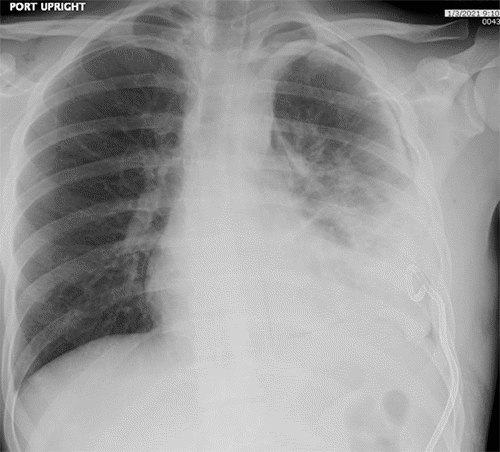

Chest tube drainage demonstrated a declining trend over the subsequent five days (Figure 11). Dietary advancement did not trigger an increase in output. Based on these findings, the chest tube was removed, and the patient was discharged home.

Figure 11. Chest X Ray, POD 5. Published with Permission

Improved left pleural effusion after repeat thoracic duct embolization